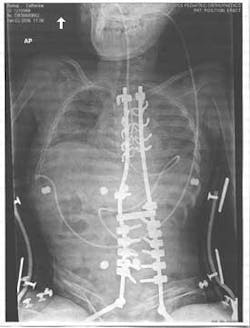

Catherine was brought to me by her foster parents, Jan and Harold Woods, facing the biggest challenge of her life. Her affliction was compromising her internal organs to the degree that she required corrective surgery to have any hope of continuing to live. Her surgeon mandated that if he was to be successful placing the titanium rods along her spine to straighten her back and increase the volume in her thoracic cavity, her body must be disease-free. Both he and her foster parents knew the oral cavity was going to be a challenge.

When I came out and told Harold we had extracted seven teeth, he just about fainted. Just days before major back surgery, my staff and I did our part to make it happen. STA was the tool that made us successful. Without our successful treatment, we don't know if Catherine would be here today. Truly, STA technology saved her life.